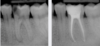

Exemple :

Une volumineuse carie s’est développée sur cette molaire inférieure. L’envahissement bactérien de la pulpe oblige le chirurgien-dentiste à nettoyer et désinfecter entièrement la cavité pulpaire (chambre pulpaire et canaux radiculaire), jusqu’aux extrémités des racines. Cet espace ainsi préparé est ensuite obturé de façon étanche (matériau blanc sur les radiographies).